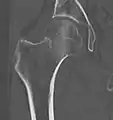

X-ray of a normal hip joint.

Fracture treated with cannulated screws

For low-grade fractures (Garden types 1 and 2), standard treatment is fixation of the fracture in situ with screws or a sliding screw/plate device. This treatment can also be offered for displaced fractures after the fracture has been reduced.

Fractures managed by closed reduction can possibly be treated by percutaneously inserted screws.[37]